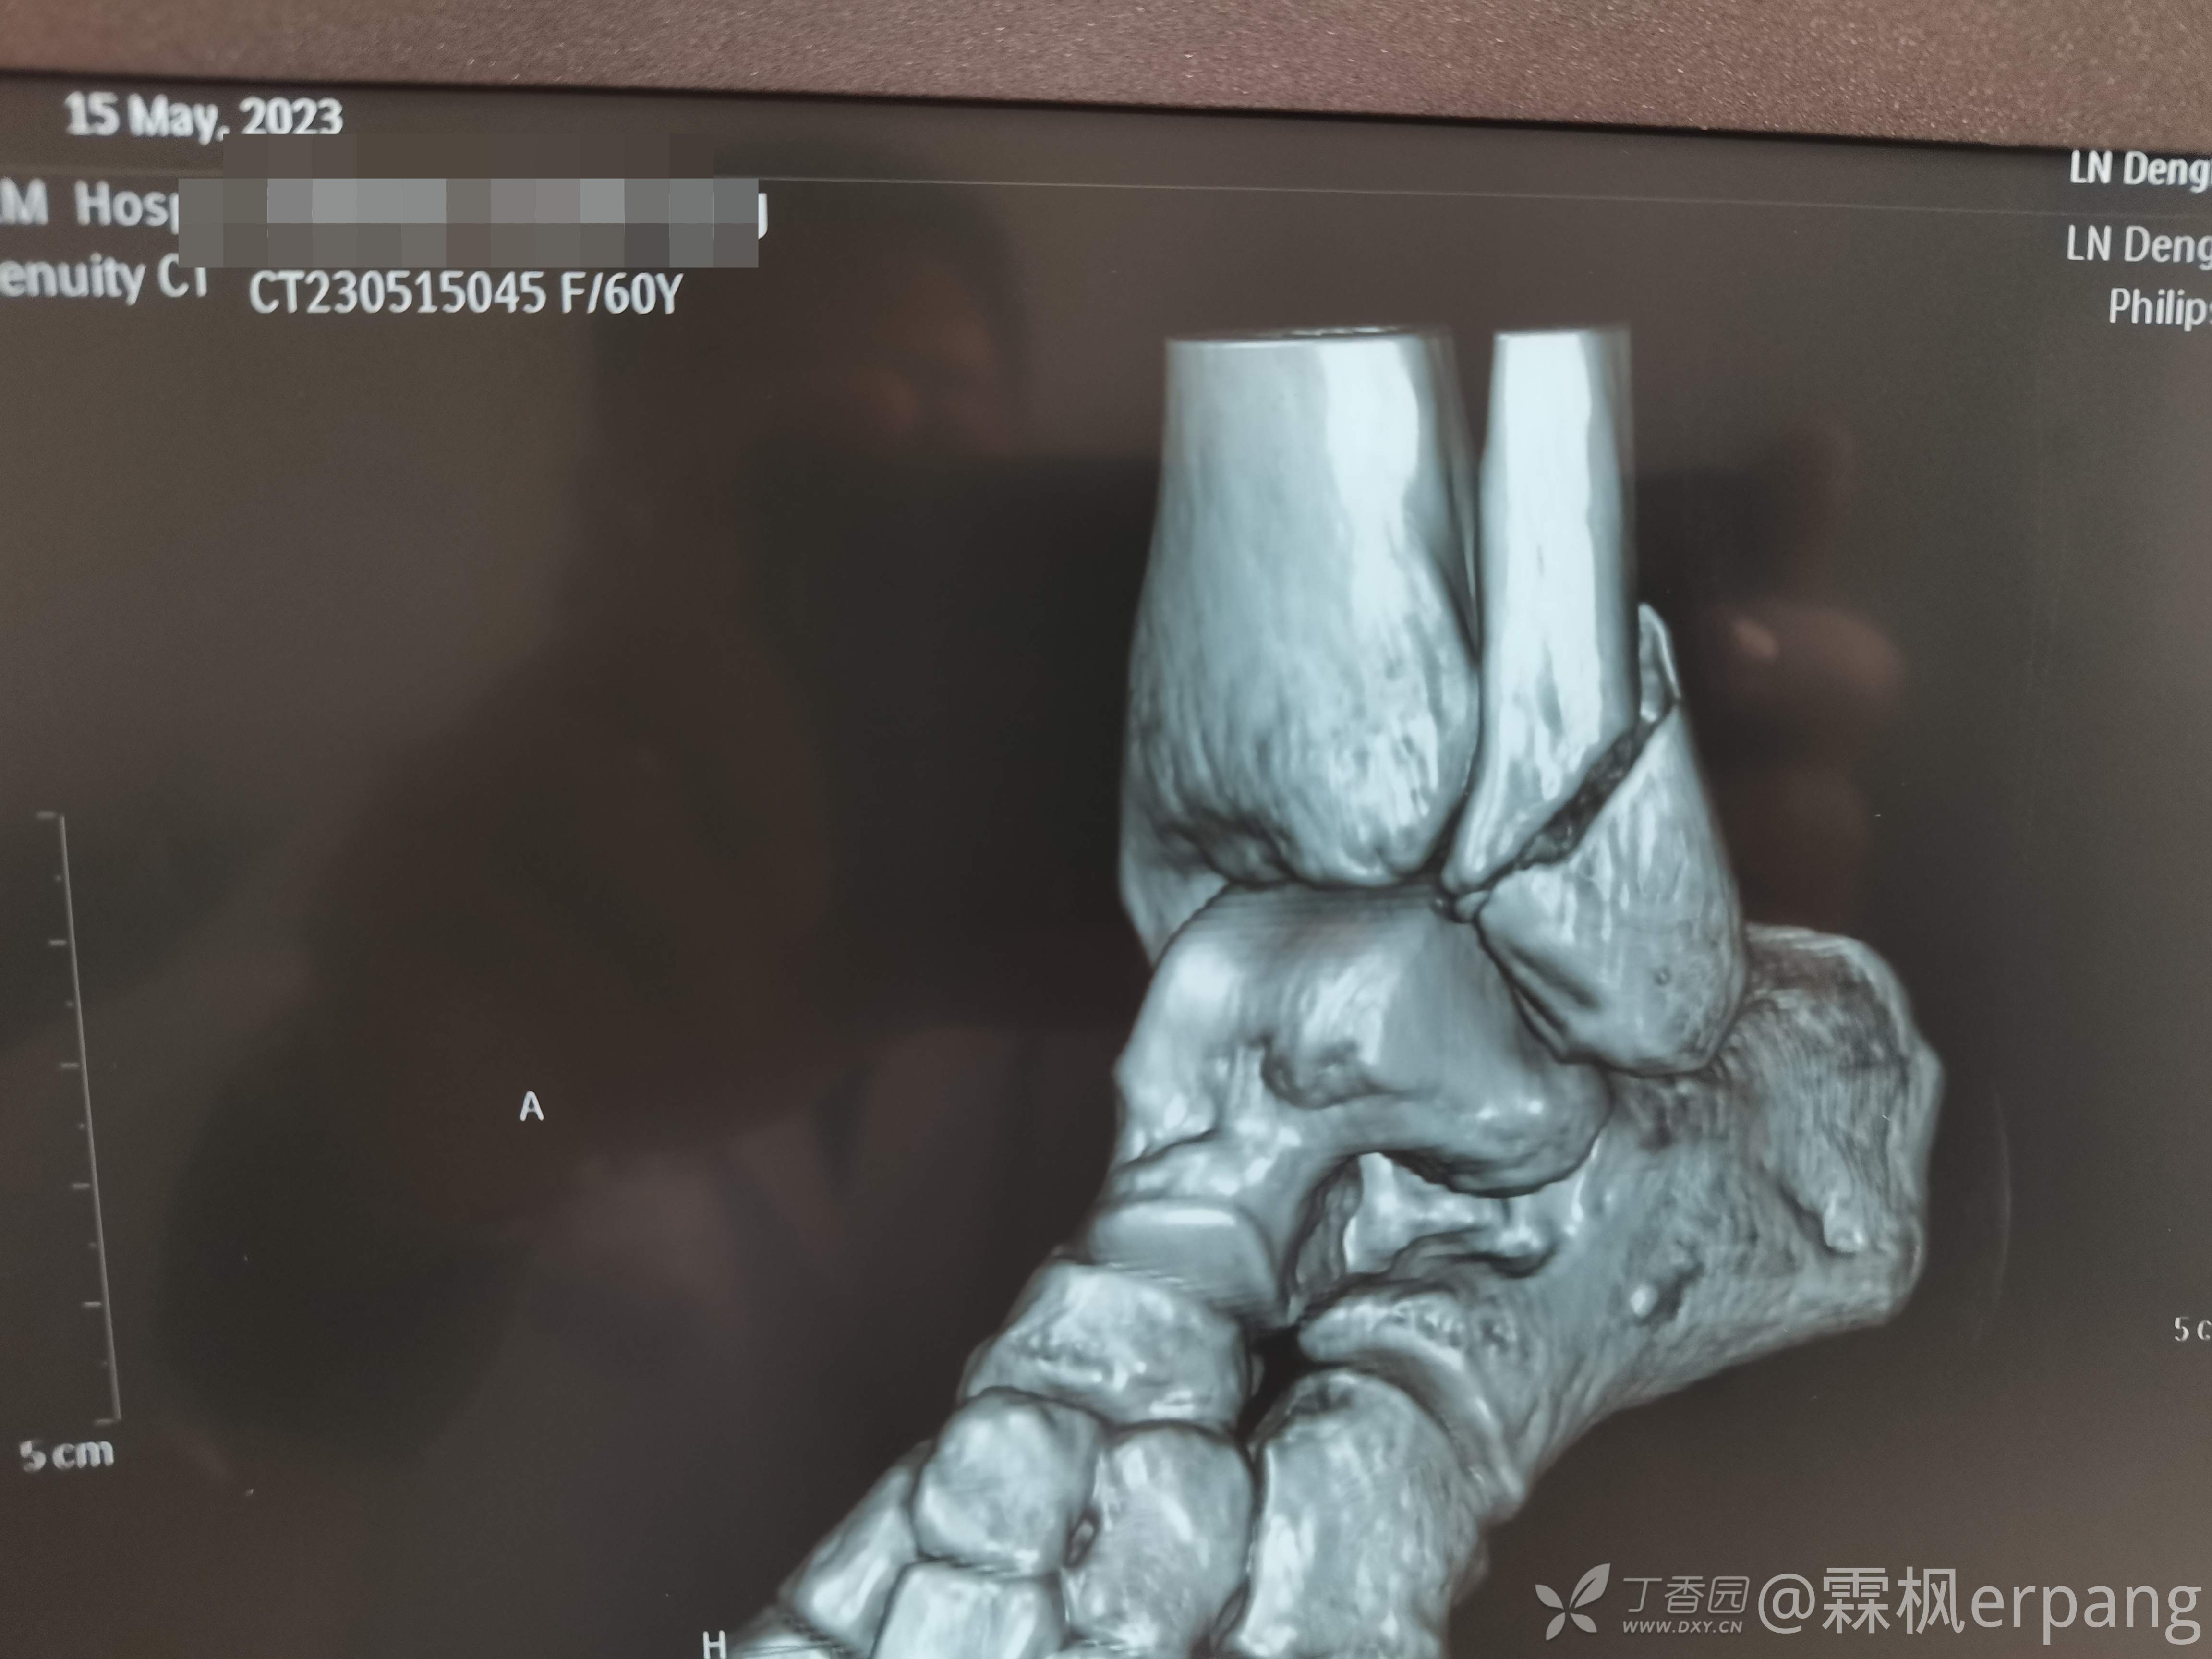

3度变4度

手术计划:后外侧切口做外踝和后踝,内侧闭合空心钉内固定。